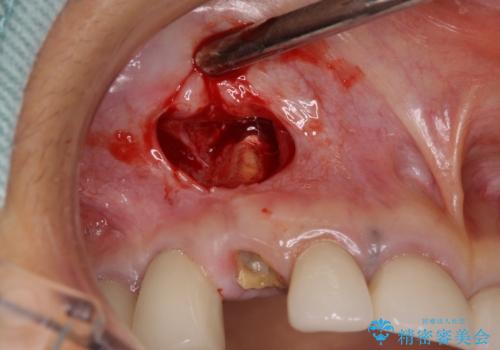

他の部位にインプラント治療を行っていたことから、こちらの歯に対してもインプラントによる補綴治療を希望されたため、1泊での帰国時に抜歯、インプラント埋入、仮歯の装着を行い、数ヶ月後の帰国時にオールセラミッククラウンの型取りと装着を行う計画としました。

インプラント埋入時は1泊、補綴治療時には3週間ほど日本に滞在していただき、2回の渡航で無事に治療を終えることができました。